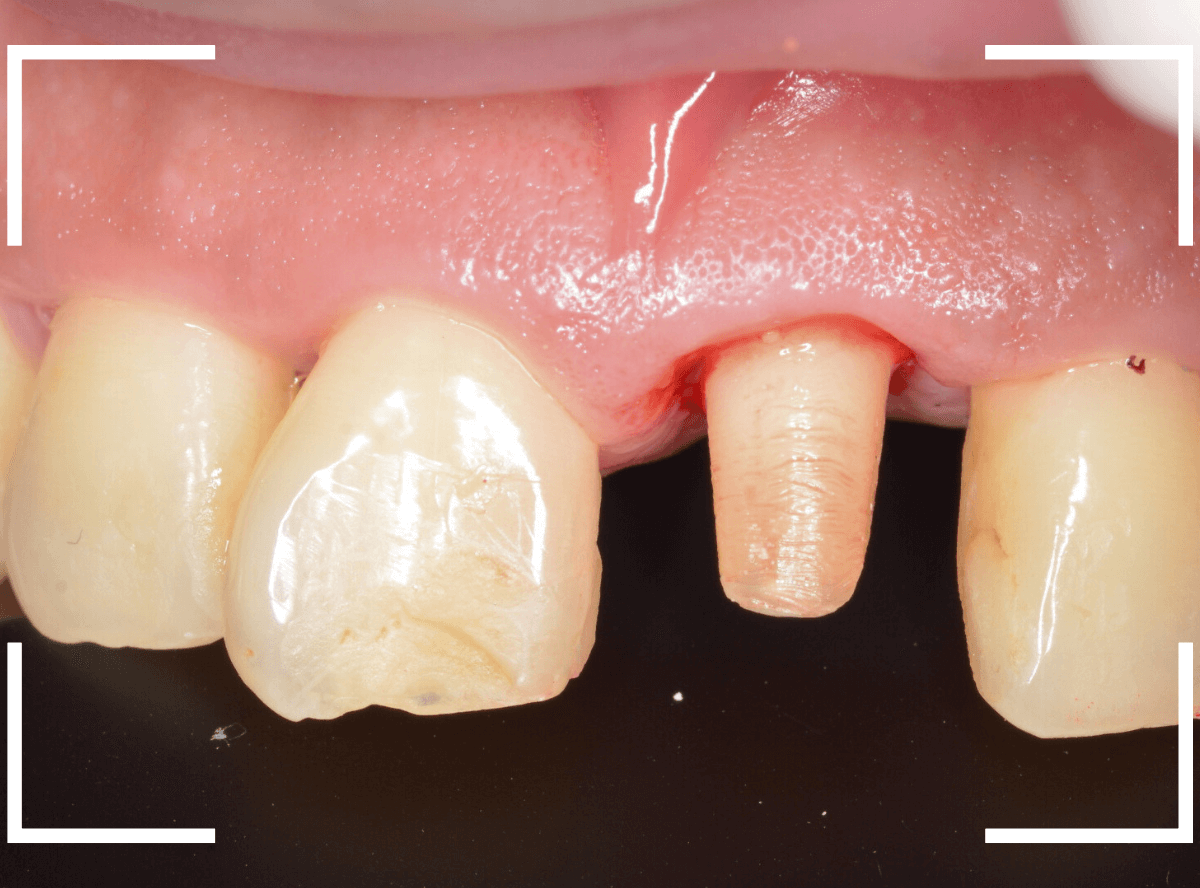

まず、歯周病の治療と並行して、神経の治療を行います。

さし歯を被せるために、歯の土台をたてて、歯を削ります。

歯の高さが低く、このままさし歯を作っても、すぐに取れてしまう事が予想されます。

隣りの歯と比べても歯肉の際が浅いため、若干歯肉を切開して、歯の高さを稼ぎます。

歯肉を切開した部分に、仮歯のレジンを盛って確認します。